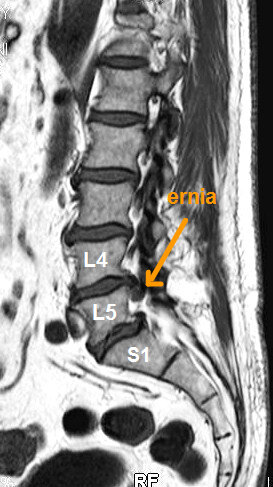

Gli veniva prescritta esecuzione di risonanza magnetica della colonna lombare. Effettuava alcune sedute di scramblertherapy, con associata terapia antidolorifica e anti-infiammatoria. La VAS (il dolore) migliorava e scendeva da 8-9 a 6-7.

Ciò consentiva una più agevole esecuzione della risonanza magnetica, che evidenziava una voluminosa ernia discale espulsa L5-S1 destra.

A distanza di 4 mesi ha effettuato una nuova risonanza magnetica lombare, che ha documentato la completa scomparsa della voluminosa ernia.

Secondo i criteri della medicina moderna non si può affermare con assoluta certezza che l’ozonoterapia eco guidata sia stata la causa diretta ed esclusiva della scomparsa dell’ernia, tenendo anche conto che la regressione di un’ernia discale può essere un fenomeno naturale e spontaneo.